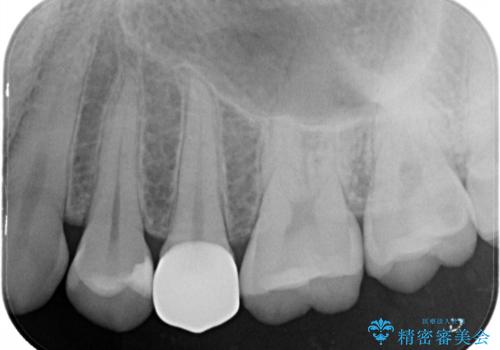

右上の被せものを除去したところ、中で歯が割れていたため、部分矯正で引っ張り出すことになりました。

・約3か月ほど引っ張り出します。

・十分に引っ張り出した後、歯肉の手術が必要となります。

・歯肉が落ち着いてから最終的な被せものの製作となります(約3か月)。